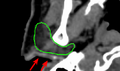

- We have 40 head and neck cancer CT images from RTOG that have manually drawn contours for the brainstem left and right parotids, as well as manually identified bony landmarks in the skeleton.